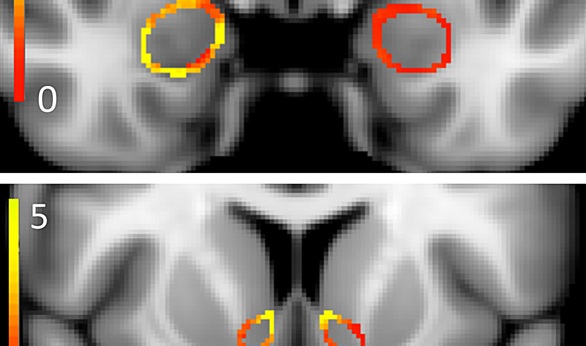

المادة الرمادية التي تراها تدعى "النواة المتكئة" وهي مركز السرور في الدماغ على شكل الجوز، تتوهج مثل للهب عندما تتعاطى الماريجوانا، إضافة إلى زيادة ملحوظة في الكثافة.

وعرضت الصحيفة دراسة في جامعة هارفارد نورث وسترن نشرت في عدد إبريل من مجلة علم الأعصاب توصلت في النهاية إلى أن الماريجوانا تحدث تشوهات في شكل وكثافة وحجم النواة المتكئة، والتي تعتبر جوهر الدافع واللذلة والألم وكل القرارات التي تتخذها.